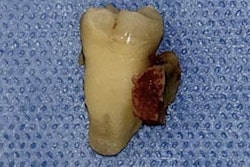

The woman, who had a fever, neck pain, and a two-week-old rotation disorder, was referred to an outpatient clinic. The woman, who had a history of chronic heart failure, paroxysmal atrial fibrillation, high blood pressure, and diabetes, and no underlying conditions or musculoskeletal abnormalities associated with neck pain, was undergoing periodontal disease treatment at a clinic. Her fever and neck pain started on the day she received periodontitis treatment, which lasted about an hour, according to the report.

Though her fever was controlled with acetaminophen, her neck pain with rotational restriction continued. Lab results showed she had elevated C-reactive protein levels but nothing else was abnormal. Other exams couldn't determine the source of the elevated levels. Her dentist ruled out an odontogenic infection, the authors wrote.